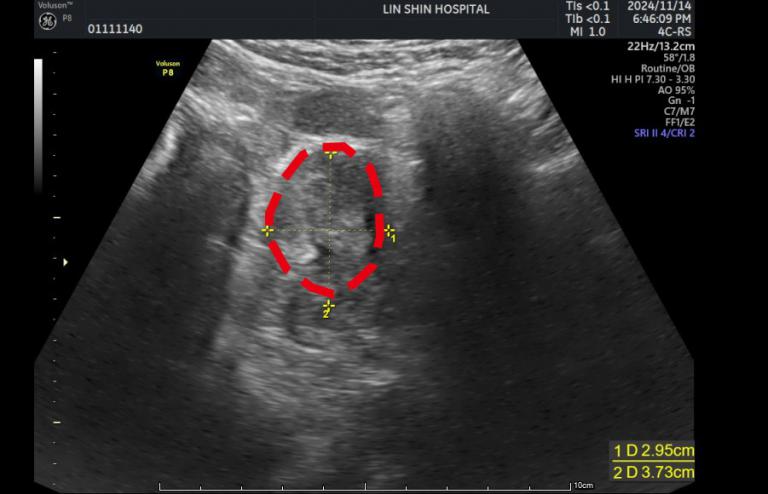

▲徐女士一個月後回診追蹤,超音波顯示肌瘤已縮小至3.7×3.6×2.9公分,體積僅剩38立方公分,約縮小近九成,大小相當於一顆小番茄。(圖╱林新醫院提供)

徐女士於113年10月7日完成手術,術後恢復狀況良好,僅住院兩日即順利出院。一個月後回診追蹤,超音波顯示肌瘤已縮小至3.7×3.6×2.9公分,體積僅剩38立方公分,約縮小近九成,大小相當於一顆小番茄。原本困擾多年的經痛及因肌瘤壓迫造成的頻尿、悶脹感,也明顯獲得改善。